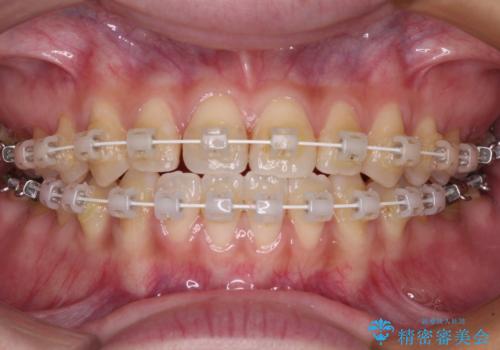

- 矯正装置

- 審美装置

- 治療期間

- 2年

マウスピース矯正も提案しましたが、しっかりと使用する自信がないとのことで、ワイヤー装置により矯正治療を行うこととしました。